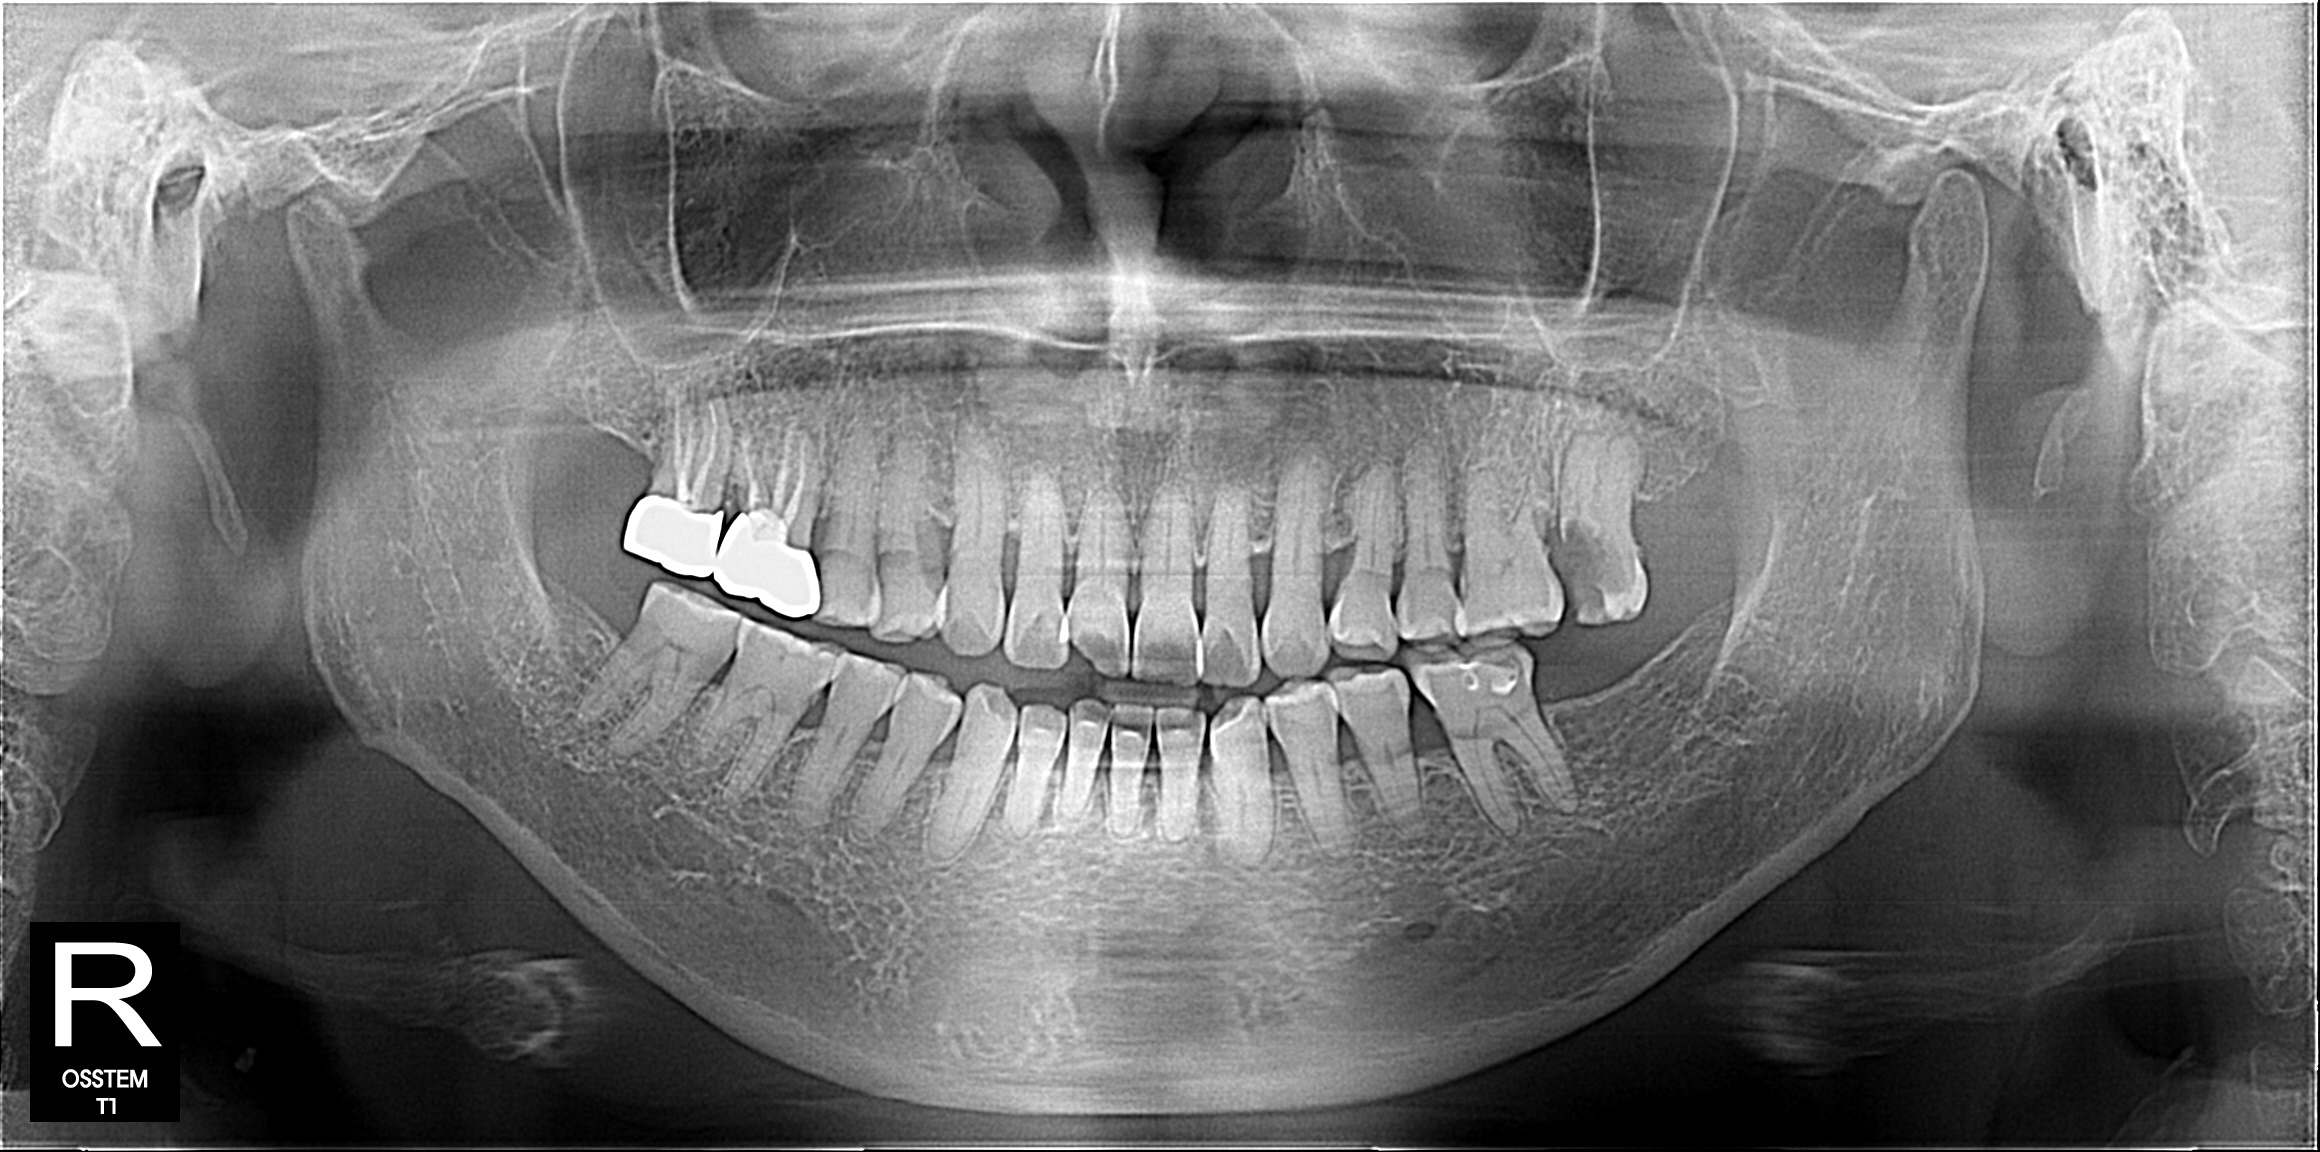

3D CT

3차원 영상으로 구강 내부를 정밀하게 확인할 수 있는 3D CT 장비를 통해 더 안정적인 진료를 제공합니다.